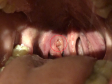

Шарик за миндалиной

Иногда жжение внутри, дискомфорт в шее, иногда ком в горле.

Здравствуйте! Подскажите пожалуйста, что это может быть ха миндалиной?

Складка слизистой на фоне хронической гиперплазии миндалины и воспаления...